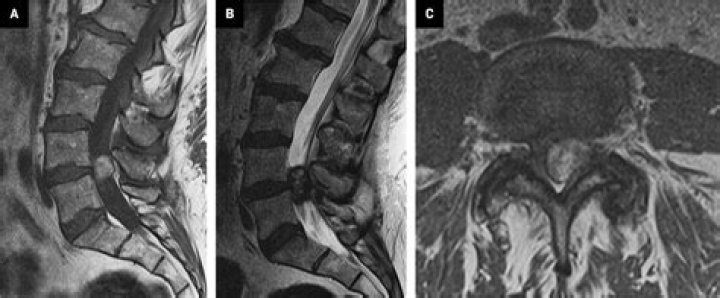

How do you detect a synovial cyst?

How are synovial cysts diagnosed? A synovial cyst is best seen with an MRI. This scan allows your doctor to see inside the spinal column and find any cysts or anything else causing your symptoms. Other imaging tests like an X-ray or ultrasound may also be able to detect the cyst.

What is a T2 hyperintense cyst?

If a T2-hyperintense mass has a thin rim of peripheral enhancement and no internal enhancement, it is a truly cystic (ie, fluid-filled) lesion. Ganglia are very common and should be considered whenever a periarticular mass with these characteristics is identified at MR imaging (Fig 1).